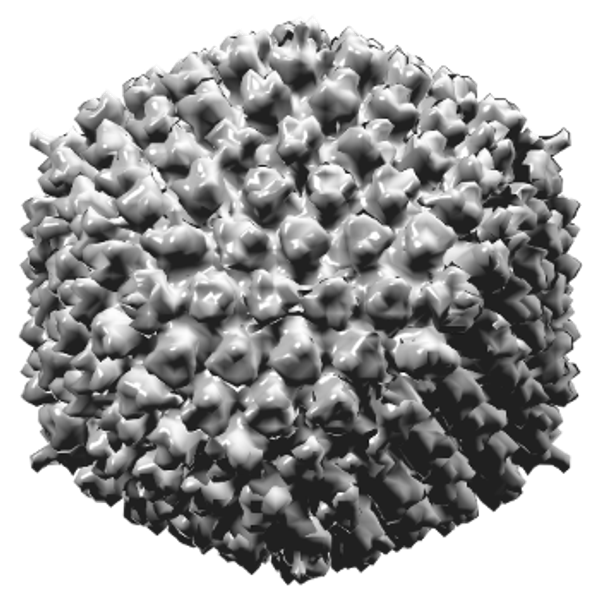

Eigenlijk is een adenovirus een heel gewoon verkoudheidsvirus en helaas is het, omdat het een virus is, niet met medicijnen te bestrijden. Dit komt omdat een virus slechts alleen een klein stukje genetisch materiaal is met daaromheen een eiwitlaagje. Dringt een virus binnen in het lichaam, en dit gebeurt meestal via het inademen van kleine druppeltjes in de lucht die iemand anders uithoest of -niest of door het aanraken van oppervlakken waarop het virus aanwezig is (bijvoorbeeld handen, deurklinken en trapleuningen), dan laat het in cellen zijn genetisch materiaal los en zet de cellen aan tot het vermenigvuldigen ervan. Het virus kaapt als het ware de cel en de cel gaat zelf viruseiwitten aanmaken die op hun beurt weer zoeken naar nieuwe cellen om te kapen. Zo breidt het virus zich razendsnel uit.

Een virus is ontzettend klein en dus niet met het blote oog waarneembaar. Je kunt dan ook nooit zien of je besmet wordt of dat een virus in de lucht of op een voorwerp zit. Leg je een virus onder een elektronenmicroscoop waarmee je meer dan een miljoen keer kunt vergroten, pas dan kun je het virus bekijken. Ter vergelijk: Een virus heeft de grootte van een voetbal op een voetbalveld dat zo groot is als heel Europa.